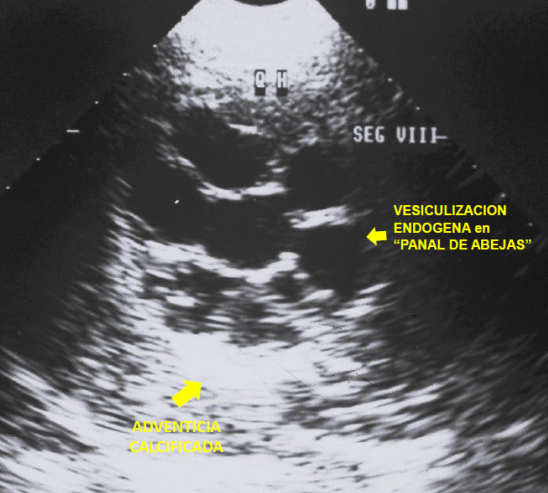

Esta comunicación muestra la correlación imagenológico-quirúrgica (Figura 1) de los estudios habituales para el diagnostico de quiste hidático en su forma crónica más frecuente: conteniendo "vesículas hijas" producto de la vesiculización endógena - responsable del signo patognomónico del “panal de abejas “ (Figura 2) - que es un indicador de vitalidad y complicación del quiste. La adventicia -muy gruesa y calcificada- se observa como una lámina blanca bien definida en la TC, (Figura 3) bajo forma de una lamina hipointensa en la RNM (Figura 4) e hiperecogénica en la ecografía (Figura 2) y corresponde a la reacción inflamatoria crónica del parénquima hepático por estimulo inmunológico de la lámina periquística hidática ,que en la evolución se infiltra de calcio .Las calcificaciones se visualizan mejor mediante TC. (Figura 3).La colangio-RNM es específica para establecer las relaciones quiste con el sistema biliar. (Figura 5)

Figura 2: Aspecto ecográfico de quiste hidático de hígado. Se observan las vesículas hijas, que dan a la lesión un aspecto de “panal de abejas” y las calcificaciones en la pared del quiste que sugieren el diagnostico .